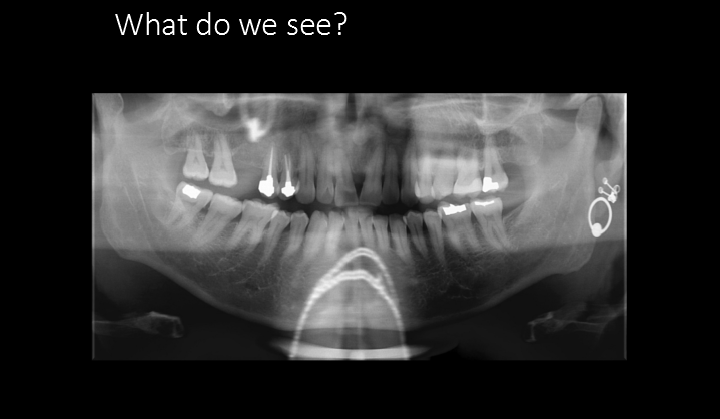

What errors do we see?

A. Chin too high and forward

B. Pt. is laughing

C. Chin too low and head too far back

D. Chin too low and head is too far forward